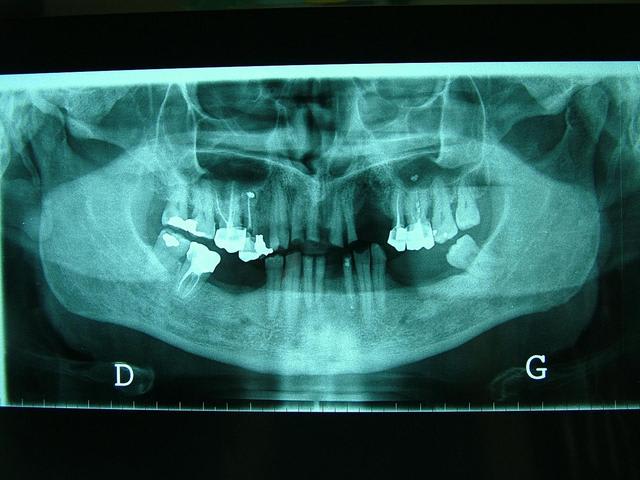

Homme de 57 ans avec DV effondrée.

faut voir comment sont ses dents residuelles,mobiles ou pas,il y a un grand manque osseux d'un (coté droit écran,je ne sais dans quel sens tu as mis la pano )extraction recente?

Pano correspond aux modèles ????

Pano inversée

Contrairement à ce qui a été dit...Il n'y a pas de perte de Dimension verticale. Les secteurs posterieurs sont plus ou moins preservés

(couronne métallique..)

Par contre dans le secteur anterieur l'usure des dents à été compensé par une egression qui donne l'illusion de perte de DV...

Le traitement est complexe car on peut pas vraiment augmenter la DV...il y pas ou peu de perte. Si on surevalue la DV, ça peut etre super mal toléré.

Oui...egressé et usée. Regarde l'os alveolaire de la pano.

Regarde aussi le collet de la 43 et 46...

De toute façon il n'y a pas perte de DV si il n'y a pas perte de calage posterieur...

Je confirme il y a un calage posterieur...presque pas de perte de DV. Donc la distance "maxillo-mandibulaire" n'a pas diminuée.

Il y a qu'a regarder la dimension verticale de repos...on saura si il y a variation de DV.